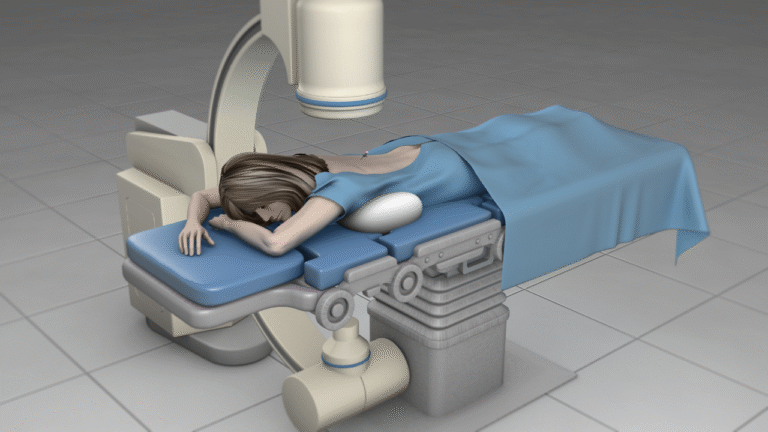

- Minimally invasive procedures

- Neuromodulation